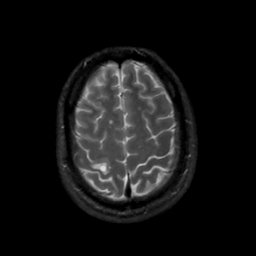

MR Study #4, March 3, 1991 -- Slice #41